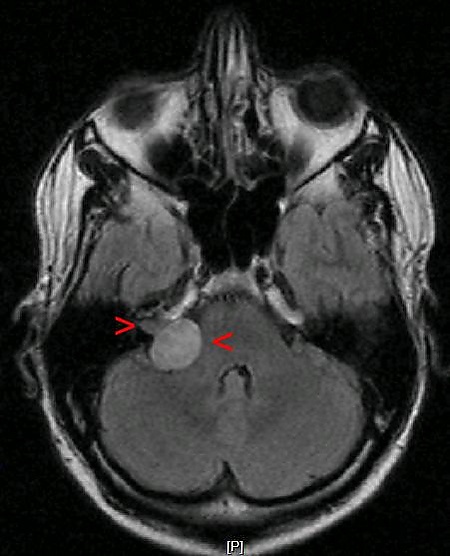

МРТ головного мозга. Невринома слухового нерва указана стрелками

Клиническая картина зависит от локализации невриномы. При наиболее часто встречающемся типе — невриноме слухового нерва она проявляется постепенным снижением слуха на одно ухо. В дальнейшем присоединяются стволовые и мозжечковые нарушения, больше выраженные на стороне опухоли. Данные симптомы вызваны сдавлением соответствующих отделов невриномой. Признаки повышения внутричерепного давления развиваются относительно поздно[2].